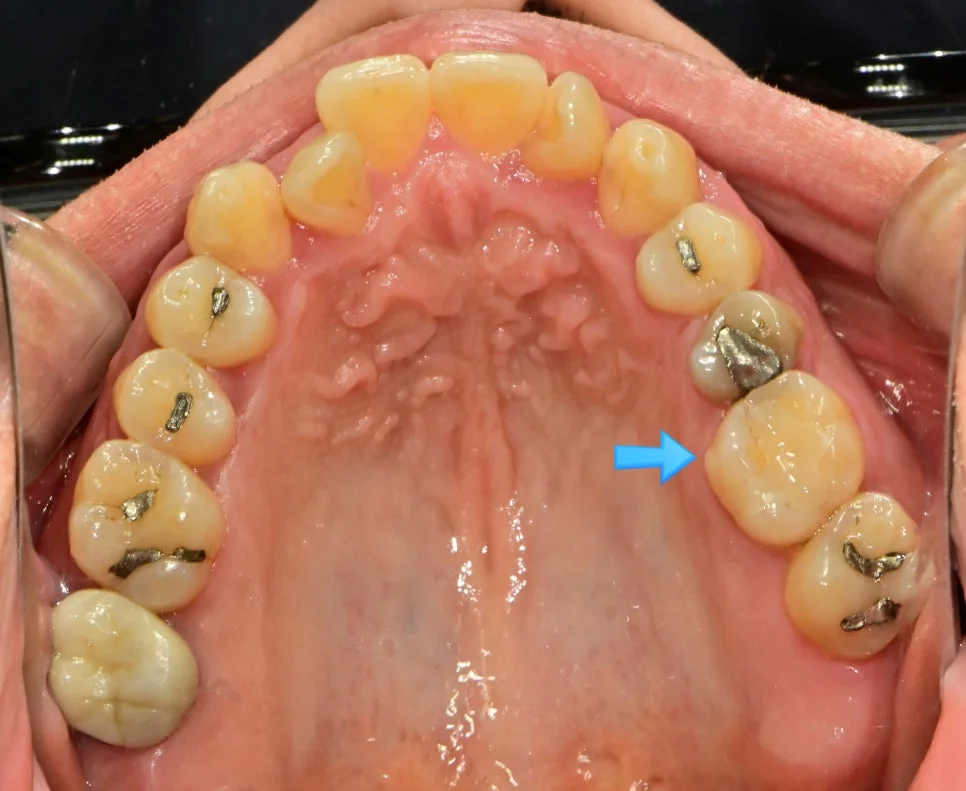

위 6, 7번째 어금니의 경우 뿌리는 3개, 신경관은 3개 혹은 4개를 가지고 있습니다. 하나의 뿌리에(MB) 2개의 신경관을 가지고 있는 셈인데, 이 중 50% 정도는 두 신경관이 하나로 합쳐집니다.

그래서 위 6, 7번째 어금니의 경우 3개의 신경관만 찾고 마무리하는 경우가 거의 대부분이죠;;

그러나 2개의 신경관이 각각 주행한다면? 그런데 3개만 찾고 신경치료를 마무리한다면? 신경관 하나를 찾지 않고 신경치료를 마무리한 셈이 되고, 결국 신경치료가 끝난 후에도 통증이 지속되는 원인이 됩니다.

(실제로 신경치료 후 통증의 가장 큰 이유는 missing canal, 즉 신경관을 찾지 못해서입니다;;)

4번째 신경관이 보여 길을 찾아보았습니다. 같이 주행하는 것처럼 보이시나요?^^